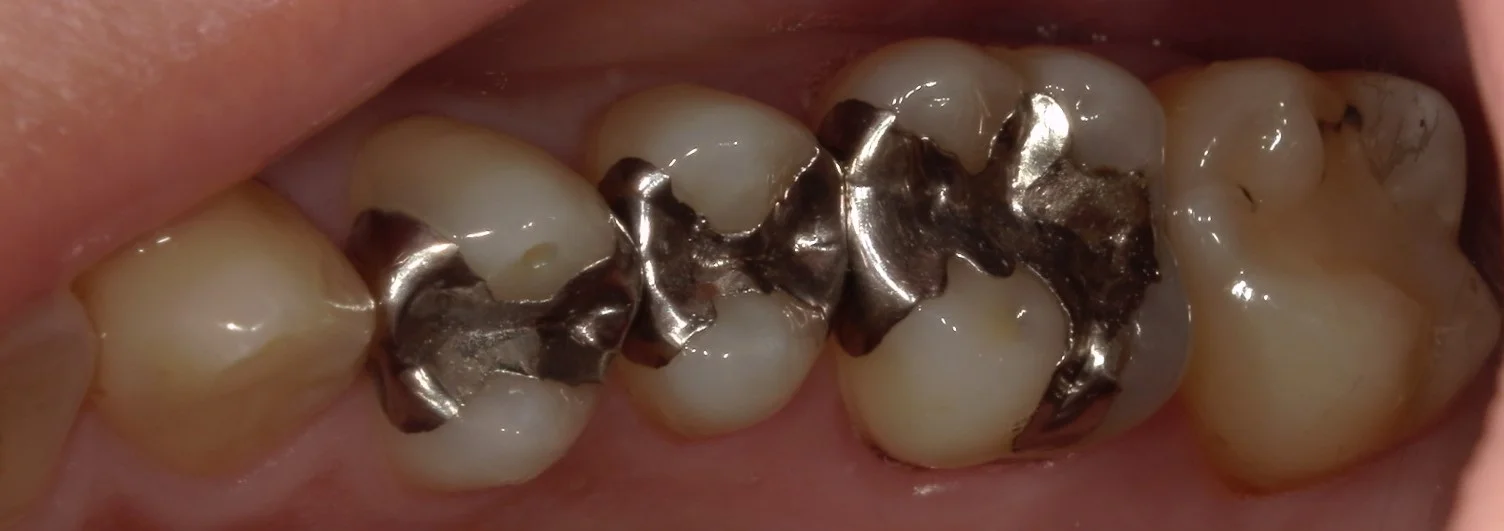

まずは術前ですね。

今回は神奈川県からの来院の為、一気に4本を行っています。

処置を行ったのは金属が入っている3本と、右側一番奥の白い詰め物が入っているところです。